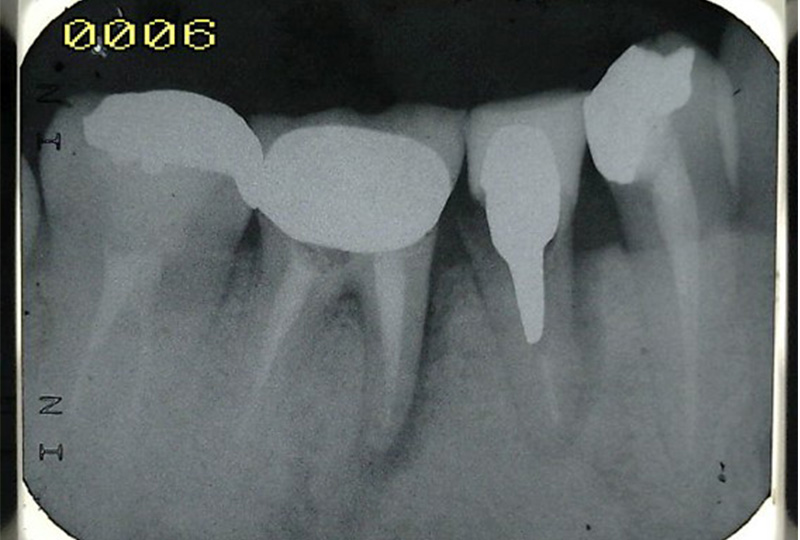

『歯のひび(歯根破折)』など通常であれば抜歯と言われるような歯の保存や歯を失った所に親知らずなどを移動させる『歯の移植』など一般の歯科医院では行わない特殊な治療も行なっております。